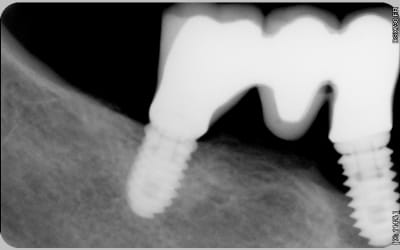

à mon tour de vous demander de l'aide, à votre avis quel est cet implant ?

J'opterais pour un MIS implant, modèle C1 en wide platform genre diamètre 5mm. Les deux implants sont les mêmes, J'aimerais garder celui en 46 et déposer celui en 44.

c'est pas les bonnes spires....elles s’épaississent sur le C1 alors que là tu as des spires triangulaires sur toute la longueur

en plus de çà la connexion n'a pas l'air d'être conique....on dirait plus une connexion "Zimmer" ou à plat....

ce que je trouvais de plus proche c'est des osstem....mais c'est une connexion conique Astra ou alors des blueskybio, mais çà correspond pas non plus parfaitement (le léger retrait au col...)

je cherche encore, est-ce que ça pourrait être un Athogyr BL REG comme celui de cette photo ?

La petite spire au col s'en rapproche... C'est ce que j'ai trouvé de plus ressemblant mais je n'ai jamais posé du Anthogyr...

Non ce n'est pas un Axiom BL.

Le trait léger retrait sous le col est perturbant.